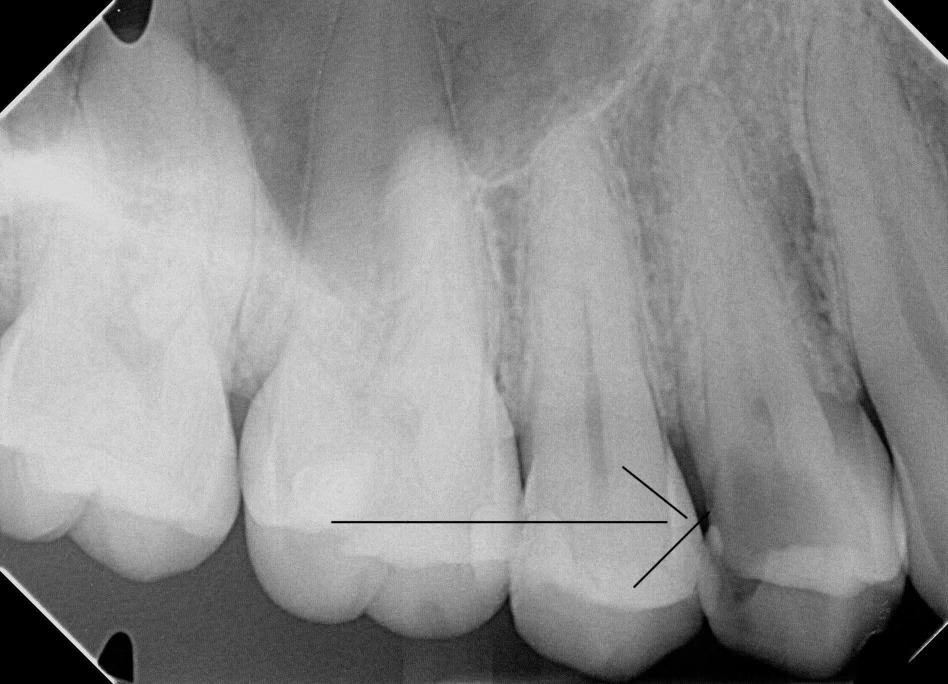

Case Study: Root Canal

Generate some text here